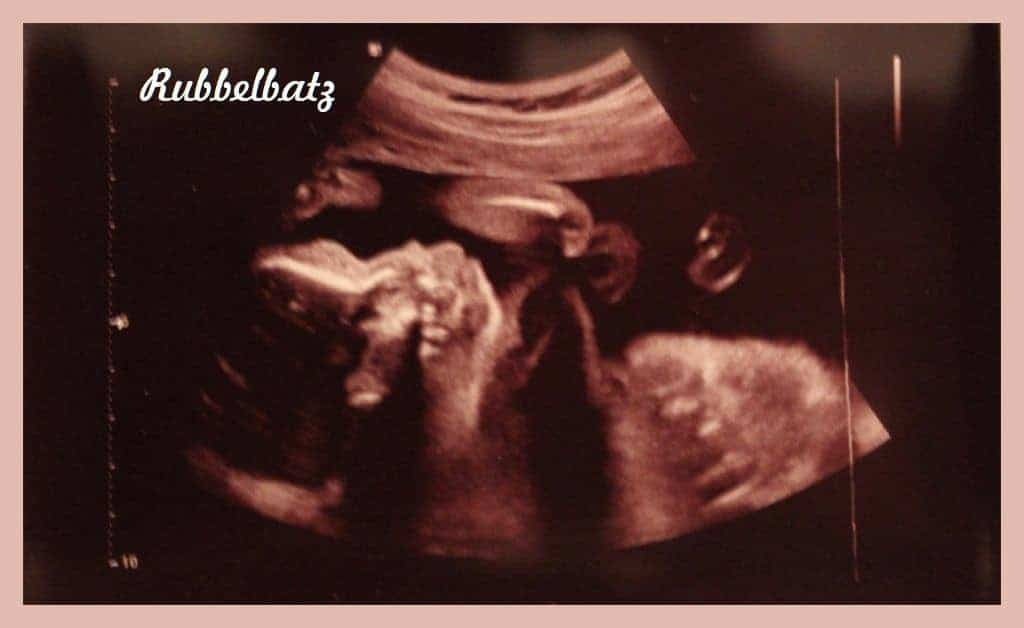

Re 3 großer Ultraschall Antwort von Mamschi15, 29 SSW am , 2125 Uhr Super Süßes Bild Und prima, dass es dem Bubi so gut geht!. Deutsche Gesellschaft für Ultraschall in der Medizin eV Neue Strahlenschutzverordnung Ultraschall in der Schwangerschaft ist gefährlich?. Bei einem chirurgischen Eingriff im Rahmen einer ProstataOP kommt es nicht bei allen Patienten zu einer vollständigen Entfernung der ProstataDiese wird hingegen so verkleinert, dass sie nicht mehr auf die Harnröhre und Blase drücktZu diesem Zweck kommen kleine Instrumente zum Einsatz, die durch die Harnröhre bis zur Prostata geführt werden.

So meine Lieben, nun hatte auch ich meinen zweiten großen Ultraschall (da ich ja bisher schon 2x zur Feinsono war und da auch noch Termine folgen ist das natürlich, in 2d, eher unspektakulär und für die, die meine Vorgeschichte kurz mitbekommen haben, ist ein Ultraschall. Doch nie vergingen die e so schnell wie in dieser Schwangerschaft Ich arbeite, hauptberuflich und nebenberuflich, und versorge nebenbei die Kinder (zusammen mit dem Mann zum Glück) und dann ist der lange Einschlafprozess von Sohn und der ist vorüber Ich vergesse so oft, das wöchentliche Bauchbild für meine private. Mögliche Komplikationen beim Ultraschall des Bauches Eine Ultraschalluntersuchung ist komplikationslos Alternative oder ergänzende Untersuchungen Mittels Ultraschall ist es möglich, die Organe im Bauch oft gut beurteilen zu können, ohne dass ein großer Aufwand betrieben werden muss und ohne dass Risiken bestehen.

Feindiagnostik In Schwangerschaft Das Erwartet Dich Beim Feinultraschall Rubbelbatz De